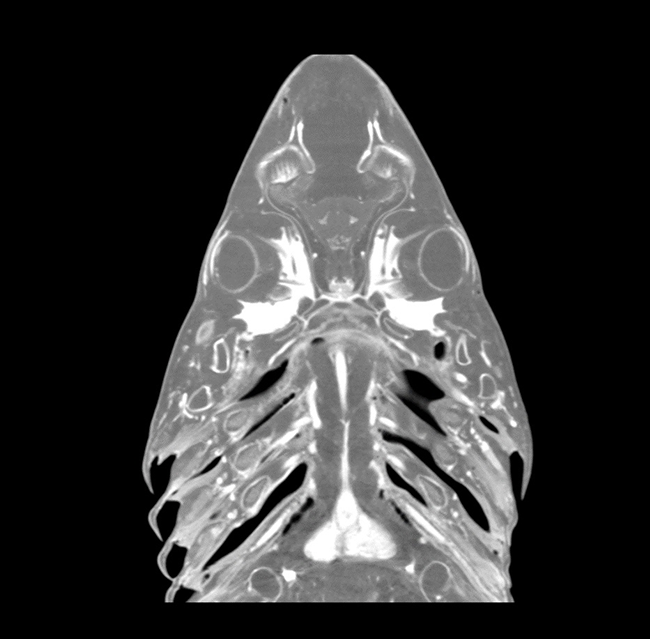

Our High Definition Volumetric Imaging (HDVI) technology is the most advanced form of Flat Panel CT technology. It delivers high-quality diagnostic imaging for both hard and soft tissues. This technology includes specific presets and customizable accessories designed for aquatic animals.

Outstanding image quality in hard and soft tissues with a spatial resolution up to 100 μ.